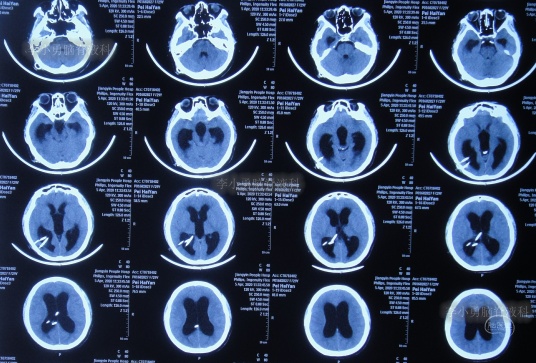

进行治疗3个月即2020年7月17日,脑积水已变完全清亮,且脑脊液化验各项指标正常,择期进行脑室腹腔分流术。

图-22:2020年7月17日

入院治疗100天即2020年7月20日,进行了脑室腹腔分流术。术后当天查头颅CT示脑室分流术后状态(图-23)。

图-23:2020年7月20日头颅CT

入院治疗109天即2020年7月29日康复出院,出院时:头晕呕吐已完全消失2月余,视物不清也变正常,睡眠也变好(图-24);出院时头颅CT示无异常(图-25)。

图-24:2020年7月29日

图-25:出院时头颅CT